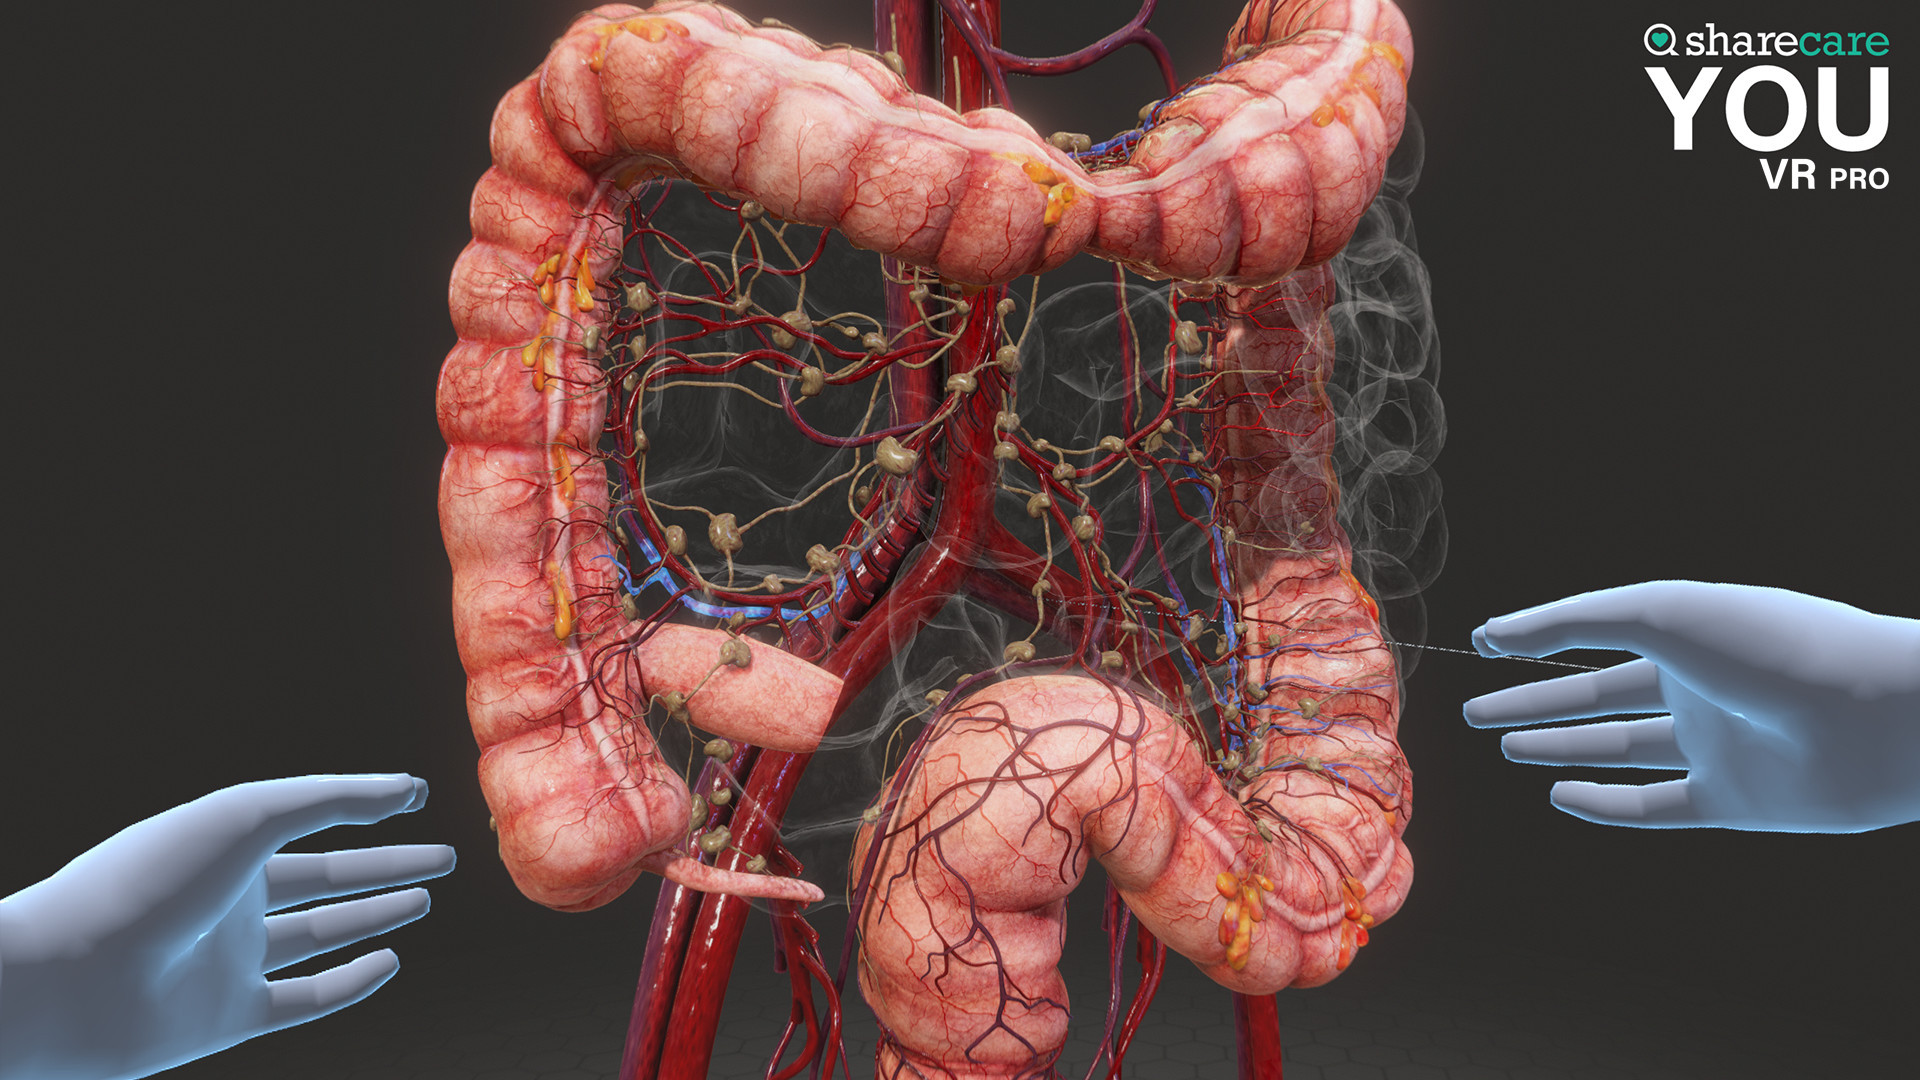

The winner of the 2019 Appy Best VR App is now available on Mac and PC, with more content, bolder graphics, and enhanced features! Sharecare YOU VR is a fully immersive, photorealistic simulation of the human body, enabling anyone to explore its astonishing details in full 360 degrees. Interested in learning about a specific organ? With the click of a button, travel inside, visualize its natural function, and dive deeper. Want to learn even more? Check out the many tags and labels along the way to gain even more information and insight. Easily customize YOU to better understand physiology and simulate disease. You can even personalize our avatars to be a virtual you – your health, your conditions. It really is all about YOU. With YOU VR PRO, users can create visually compelling, high-quality educational content. Build YOU lectures and presentations easily, with the help of video and voiceover recording, and the ability to draw and add your own text. You can also be the star within these videos using our web-cam feature.

- YOU content - an expanding library of over 40 different scenes to explore including anatomy, physiology, conditions, and treatments

Looking to use the content for Business Purposes? Get the Sharecare YOU VR Pro version and have the ability to use all the amazing content for Business Purposes. Take advantage of breathtaking graphics and never seen before views of the human body. Your ability to better communicate human anatomy and physiology with your customers and/or students is at your fingertips!